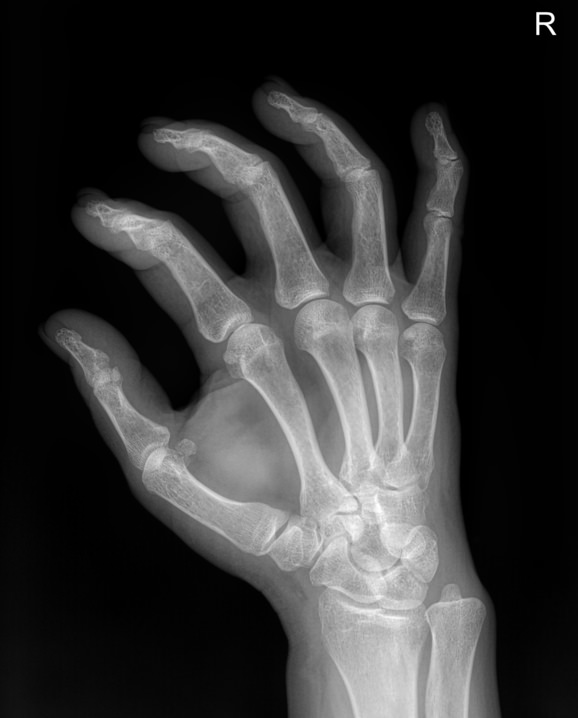

Ладонь и пальцы ― один из самых сложных участков в организме человека. Здесь сосредоточено огромное количество мелких суставов, каждый их которых может воспалиться или быть поврежденным в результате профессиональной деятельности и спорта. Изменения, связанные с возрастом или хроническим заболеванием, также влияют на состояние и функции кистей рук.

Болезни кистей серьезно ухудшают качество жизни, поэтому такие патологии редко игнорируют. Однако их симптомы схожи, что требует тщательной диагностики перед тем, как выбрать метод лечения. Одно из базовых исследований ― рентгенологическое. Это простое, быстрое, информативное и недорогое исследование. Современное цифровое оборудование, которое используют в клинике «Доступная медицина», во время процедуры несет минимальную дозу облучения. Это делает рентген практически безопасным методом обследования.

Что показывает рентген кисти

В протоколе рентгенолог описывает изменения, которые произошли в области исследования:

• Состояние суставных щелей;

• Соответствие друг другу суставных поверхностей;

• Патологические изменения поверхности суставов;

• Состояние костной ткани ― травматические и дегенеративные деформации;

• Возможные новообразования;

• Мягкие ткани.